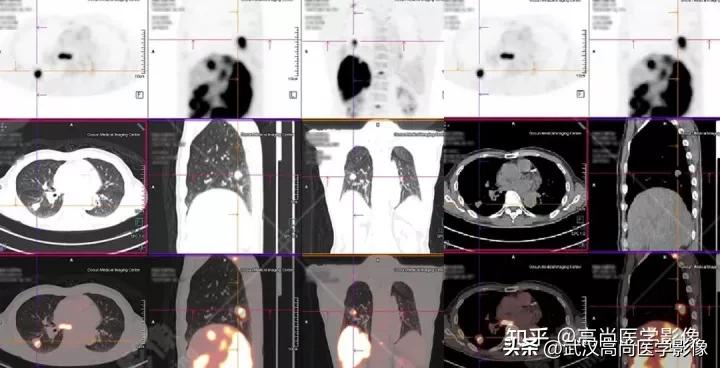

影像表现:

右肺下叶背段见一实性结节,大小约2.0cm×1.6cm×1.8cm,CT值33Hu,FDG高摄取,SUVmax13.0。

恶性CT征象:

病灶边缘分叶、短毛刺,其近端亚段支气管截断,瘤肺界面清楚,病灶远端片絮状阻塞性炎症。

PET/CT诊断结论

右肺下叶背段周围型肺癌,伴多发淋巴结、左侧小脑半球、肝脏、骨多发转移。